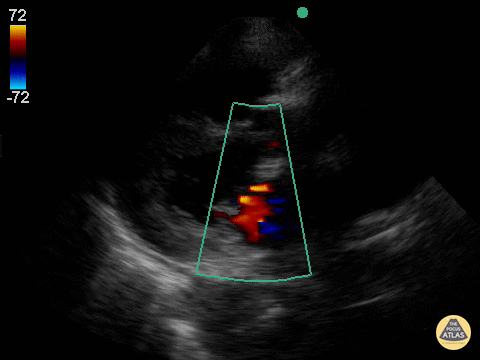

This was a patient who presented at the age of 98 who had become progressively more short of breath over the last several months and now had trouble getting around. Very sharp and witty woman, who wished to have no aggressive measures. She was tucked into the cardiology service for gentle diuresis and optimization of her heart disease. This parasternal long axis demonstrating alternating mild-moderate aortic regurgitation with moderate mitral regurgitation.